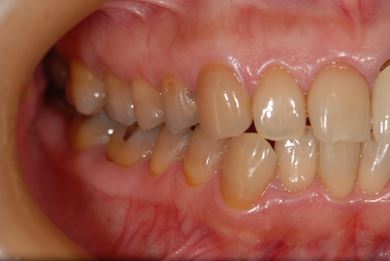

セラミック治療+ラミネートベニア治療

| 主訴 | 虫歯を白い詰め物で治療したい。全体的に歯の色が気になるので、ホワイトニングをしたい。ホワイトニングの効果がなければ、セラミック治療を受けたい。 | ||||||||||||||||||||||||||||||||

| 治療方針 | セラミック治療にて、審美的回復を行う。 | ||||||||||||||||||||||||||||||||

| 治療内容 | ジルコニアオールセラミッククラウン1本(オールセラミック用土台1本)、オールセラミッククラウン9本(オールセラミック用土台1本)、オールセラミックラミネートベニア11本 | ||||||||||||||||||||||||||||||||